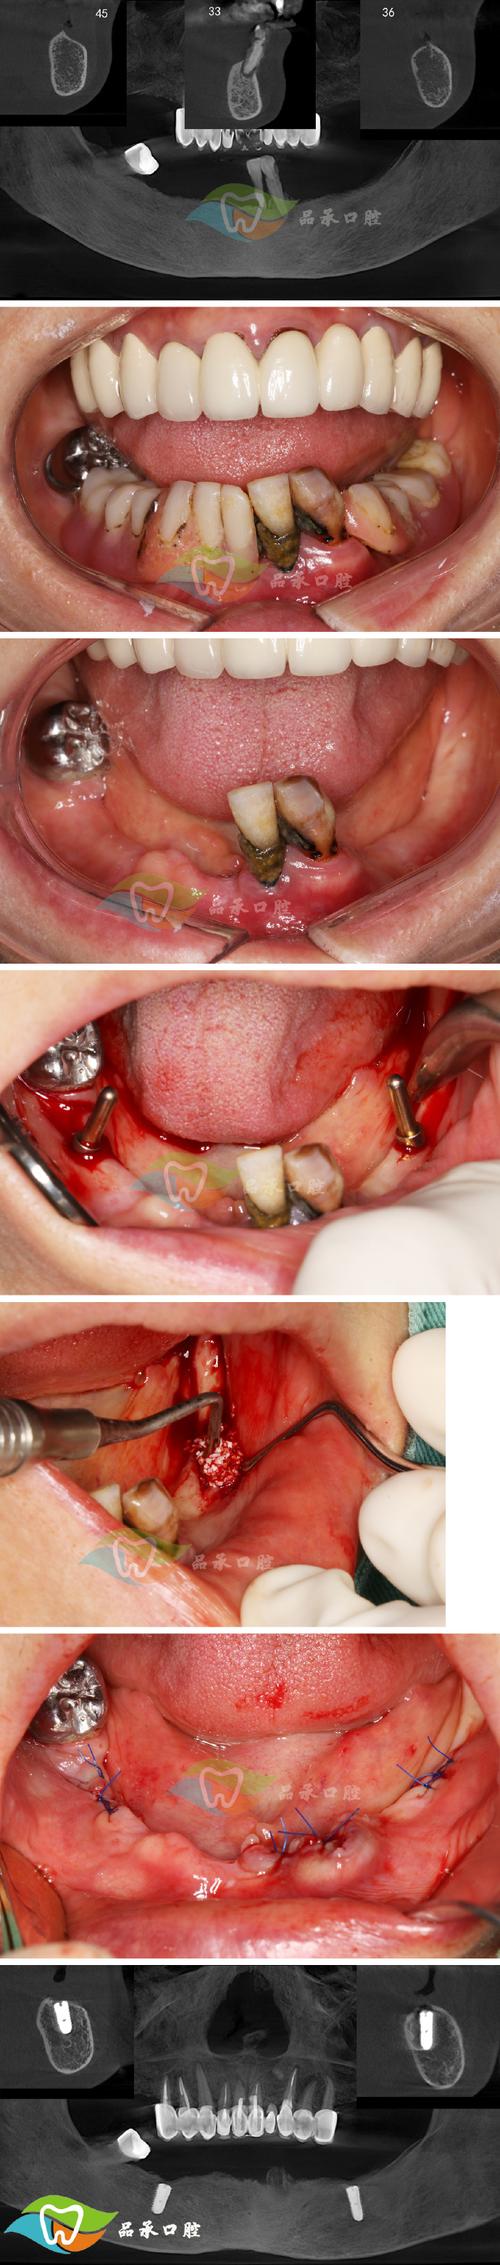

- 骨量评估不足:术前未做CBCT精准扫描,牙槽骨厚度、高度不够却未植骨,导致种植体初期稳定性差,后期受力后松动脱落;

- 植入位置偏差:种植体穿入上颌窦、下牙槽神经管,或角度不当,导致咬合力分布不均,长期受力后基台松动、牙冠脱落;

- 临床检查:查看口腔内创口情况、是否有炎症、种植体残留;

- 影像学检查:拍CBCT或X光片,观察种植体周围骨量、是否有断裂、位置是否正确;

- 口腔检查:CBCT(观察牙槽骨厚度、高度、密度)、牙周检查(是否有牙龈炎、牙周炎,需先治疗);